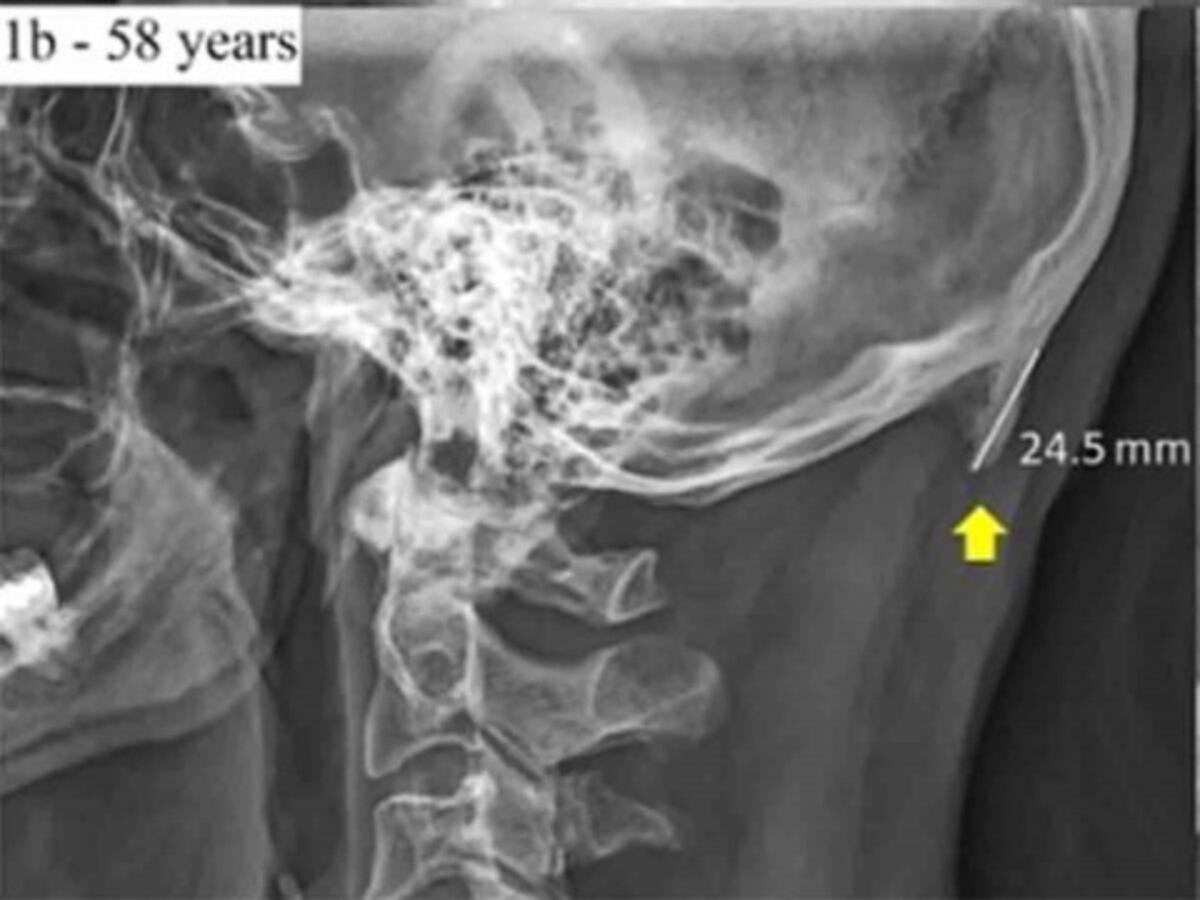

David Shahar, científico encargado de la investigación, reveló que existe una tendencia al crecimiento de una pequeña protuberancia en forma de pico en el cráneo humano.

Este bulto, indica, puede sentirse al tacto y, con la calvicie, puede resultar visible a simple vista.

Un 41% de los sujetos muestra revelaron el pequeño pico de más de 10 milímetros.

Shahar afirma que esto es debido a la inclinación que ejercemos para poder ver las pantallas de nuestros celulares pues, existe esto tensa los músculos para sostener la cabeza que tiene un peso aproximado de unos 5 kilogramos.

Con esta presión ejercida durante mucho tiempo se puede provocar la aparición de este pico, afirmó el científico.